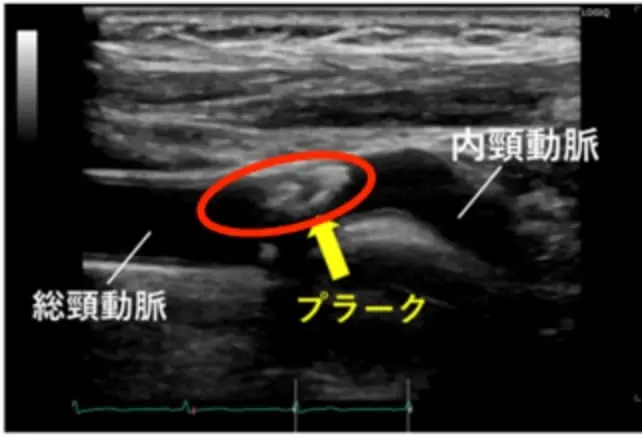

頸動脈エコー検査

首にあてた超音波が頸動脈まで届き、反射した波(反射波)から動脈硬化の程度を調べる検査。動脈壁の厚さやプラークの大きさ、動脈の狭窄度などが分かる。 ( IMCの厚みが1.1mm以上になるとプラークの疑いがある )